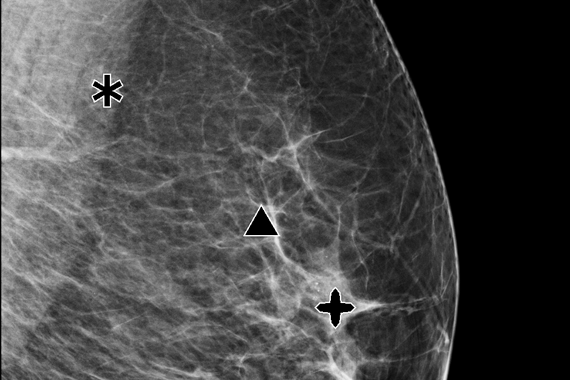

Clarity HD Yüksek Çözünürlüklü Görüntüleme ile Tanıda Netlik

Clarity HD™ teknolojisi, Hologic’in dijital mamografi sistemlerinde yer alan yüksek çözünürlüklü 3D görüntüleme teknolojisidir. Bu sistem, meme dokusunu 70 mikron çözünürlükle katman katman tarayarak olağanüstü netlikte tomosentez görüntüleri sunar. Sonuç: daha doğru tanılar, daha az tekrar çekim ve daha güvenli tarama kararları.

Özellikle yoğun meme dokusuna sahip hastalarda, Clarity HD, dokuların üst üste binmesini önleyerek küçük kitleler, gizli kalsifikasyonlar ve diğer anormalliklerin (örneğin spiküler lezyonlar veya distorsiyonlar) daha görünür hale gelmesini sağlar. Bu da erken evre meme kanserinin tespiti açısından kritik öneme sahiptir. Geleneksel 2D sistemlerle karşılaştırıldığında, Clarity HD ile elde edilen görüntü netliği %50’ye kadar artarken, belirsiz tanılar nedeniyle istenen ileri görüntüleme oranları %40’a kadar azalmaktadır.

Radyologlar için sağladığı avantaj yalnızca görüntü kalitesiyle sınırlı değildir. Clarity HD’nin yüksek hızda veri işleme yeteneği, görüntüleme süresini kısaltarak iş akışını optimize eder.

• Bernardi D. et al., “Performance of screening with digital breast tomosynthesis vs. standard digital mammography: a study of Clarity HD high-resolution imaging.” European Radiology, 2020.

→ Clarity HD teknolojisi ile lezyon tespiti %29 oranında artarken, tekrar çağırma oranı %37 azalmıştır.